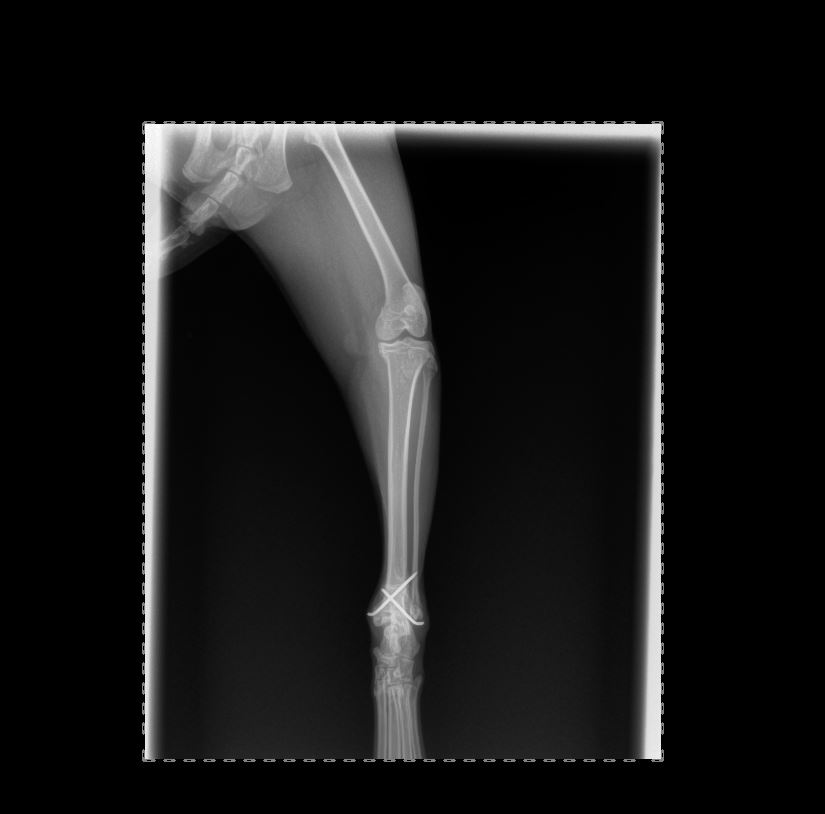

Chirurgies orthopediques:

-réduction des fractures (pose divers implants plaques broches etc),

-rupture du ligament croisé (prothèse ligamentaire)

Pose implant plaque DCP

Pose broche en "X" fracture femur en "Salter"